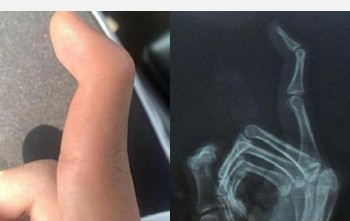

科室在肢體嚴重撕脫創(chuàng)傷、復雜斷指(肢)再植、各類型游離足趾移植拇手指再造或組合再造、游離皮瓣修復四肢缺損創(chuàng)面等方面取得顯著成績,受到了省內外專家和廣大患者高度評價。近年來,科室不斷拓寬診治范圍,深耕手病?,如腱鞘炎、周圍神經(jīng)損傷、肌腱修復等,在腕關節(jié)鏡微創(chuàng)治療方面取得了長足的進步,形成了自己的治療特色。

◎ 斷指(肢)再植 ◎ 游離足趾移植拇手指再造或組合再造

◎ 手部疾病:腱鞘炎、周圍神經(jīng)損傷、肌腱修復等

擅長:四肢顯微修復及功能重建;特殊類型斷指(肢)再植,小兒斷指再植;拇手指全型再造;小兒手足先天性畸形矯形、燒傷瘢痕整形;四肢骨缺損、手部各種腫瘤、周圍神經(jīng)損傷的診治;腱鞘炎、周圍神經(jīng)損傷、肌腱修復等;腕關節(jié)鏡的微創(chuàng)治療